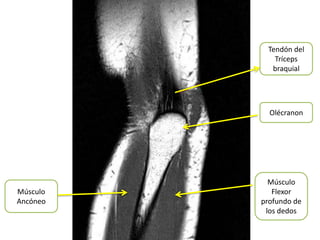

Tendón del

Tríceps

braquial

Olécranon

Músculo

Músculo      Flexor

Ancóneo   profundo de

los dedos